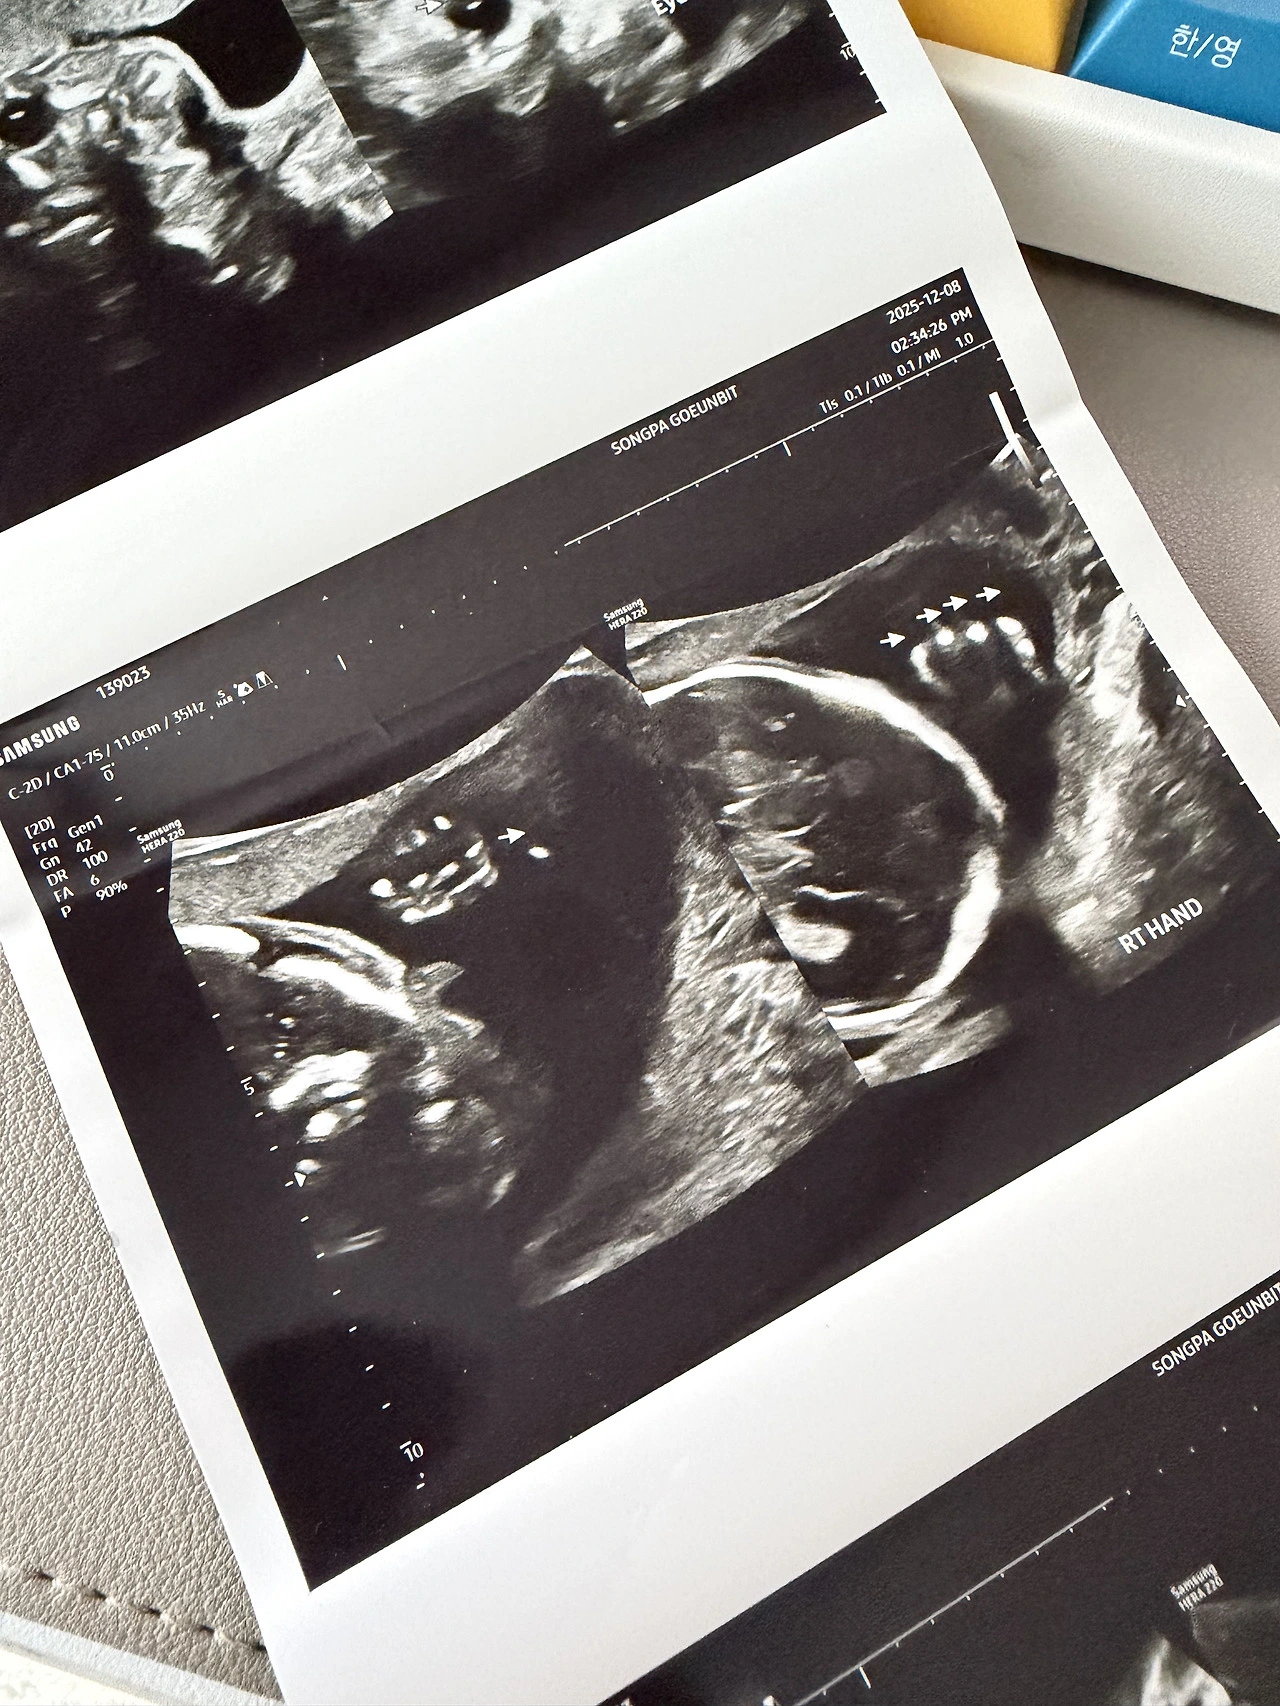

드디어 정밀초음파를 보는 날이 되었다. 난임병원과 분만병원의 커뮤니케이션 이슈 때문에 1차 기형아 검사때 대부분 한다는 정밀초음파를 보지 못해서 조금 불안했었는데 이번에야 말로 볼 수 있어서 정말 다행이었다. 정밀 초음파는 아기가 협조하는 가정하에 20분 남짓 보는데 주로 심장의 발달에 대해서 주의깊게 본다. 좌심방 우심실.. 판막.. 이런 생물시간에 들었던것 같은 용어들을 오랜만에 들어 볼 수 있었다.

눈과 귀가 제대로 있는지 입도 잘 생겼는지 손가락 발가락도 5개씩 잘 발달했는지를 낳기도 전에 초음파로 미리 확인 할 수 있다고 하니 임신 기간 내내 더 없이 좋았다. 더욱이 첫 정밀 초음파이다보니 기대보다는 걱정이 좀 더 많았던 것이 사실이다. 아기가 잘 협조해 준 덕분에 20분 남짓 빠르게 정밀 초음파를 볼 수 있었고 사실 이 중에 10분은 심장을 세밀하게 봐서 엄마가 봐도 잘 모르는 부분이 대부분이다.

정밀 초음파를 보고나면 되게 긴 용지를 뽑아준다. 보니까 이거 들고 만삭 사진 많이 찍던데 그래서 일단 구겨지지 않게 잘 펴서 보관중이다. 사진을 참 많이 뽑아주는 병원인데 초음파 앨범으로 만들고 있는 책에는 한 장 밖에 안넣고 있어서 버릴때 마다 좀 미안하긴 하다.